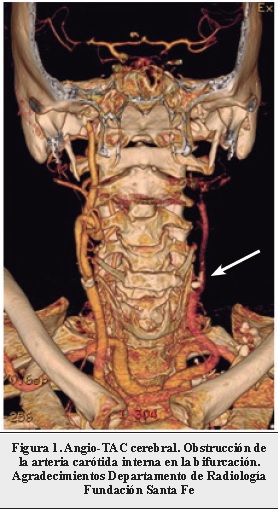

Paciente de 79 años que se encontró en el piso de su casa el día del ingreso con relajación de esfínteres y disartria marcada; la última vez que se le vio bien fue el día anterior. Se trasladó en ambulancia y se halló una hemiparesia derecha. En urgencias estaba alerta, con una afasia no fluída y hemiparesia derecha, reportaba antecedente de hipertensión arterial y diabetes tipo 2. Se llevó a una tomografía de cerebro en donde se observó un infarto del territorio de la arteria cerebral posterior izquierda, se practicó un angio-TAC en el que se descubrió una oclusión de la arteria carótida interna izquierda desde su origen luego de la bifurcación en el bulbo carotídeo (Figura 1). Se realizó una resonancia magnética que evidenció un infarto en la ubicación de la arteria cerebral posterior y de la arteria coroidea anterior en el lado izquierdo (Figura 2), con infarto talámico, del brazo posterior de la cápsula interna e infarto del uncus del hipocampo. Con una hipoplasia de las arterias cerebrales posteriores en su porción P1, con presencia de variante fetal de la arteria cerebral posterior en forma bilateral (Figura 3).

Como conclusión, al presentar este caso se hace énfasis en que para que exista un infarto de arteria cerebral posterior por compromiso de la arteria carótida se tienen que dar algunas condiciones propias de la enfermedad que lleva a la oclusión de la arteria carótida. Entre estas está en primer lugar la disección vascular o la oclusión embólica por fuente cardíaca. Adicionalmente deben existir variantes anatómicas como hipoplasia del segmento pre-comunicante de la arteria cerebral posterior o la variante fetal de la arteria cerebral posterior.